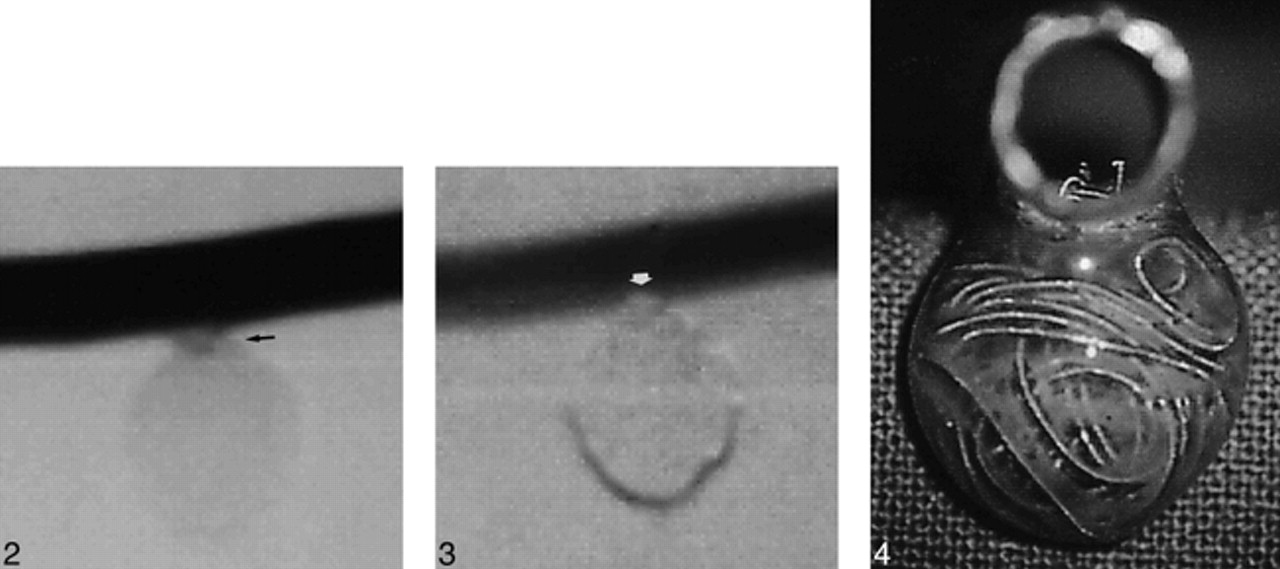

The aneurysm model was then connected to a circulatory system and to a pump (Drapier, Collin, France), which provided a pulsatile flow. Pressure values delivered by the pump were set to match physiological conditions. The circulating fluid (normal saline solution) was kept at 37°C. Under fluoroscopic guidance, the Tracker-18 microcatheter was navigated to the aneurysm's orifice. Dense packing of the aneurysm was then attempted with the mechanically detachable spiral platinum coils (DCS-18, William Cook Europe A/S, Bjaeverskov, Denmark). Digital subtraction angiography was performed after each coil was introduced. Minimally dense packing was considered to occur when circulation within the aneurysm appeared to have ceased angiographically (Fig 2). Maximally dense packing was defined as the point at which introduction of an additional coil caused slight protrusion into the parent artery (ie, the point at which more coils could not be safely placed using the standard technique of coil embolization) (Figs 3 and 4). Dense packing was achieved in four aneurysms, two small and two large. Calculation of the total volume of the coils introduced into each aneurysm was based on a 0.015-inch diameter, corresponding to 1.140 mm3/cm of coil. Then the volumetric ratios of minimally and maximally dense packing with respect to the actual aneurysmal volume were calculated.

Fig 2. Digital subtraction angiogram of model 2 after minimally dense packing (total coil length, 134 cm; ratio, 32.51%). Some diluted contrast medium is seen at the neck, attesting to the suboptimal filling of the sac (arrow).Fig 3. Digital subtraction angiogram of model 2 after maximally dense packing (total coil length, 149 cm; ratio, 36.15%). The orifice of the aneurysm is occluded (arrow).Fig 4. Tangential view of model 2 after maximally dense packing. Slight coil protrusion is seen within the parent vessel lumen